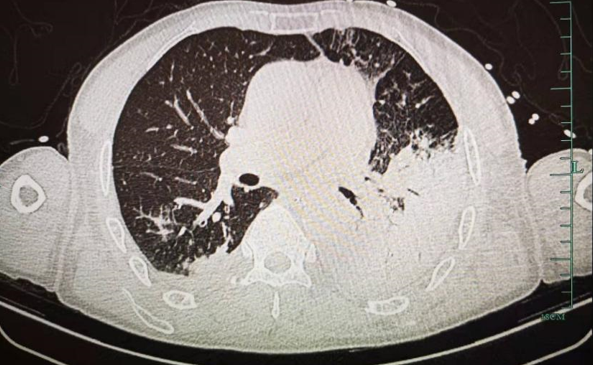

帮忙看看这个ct

入科前胸部ct(2020.02.01)